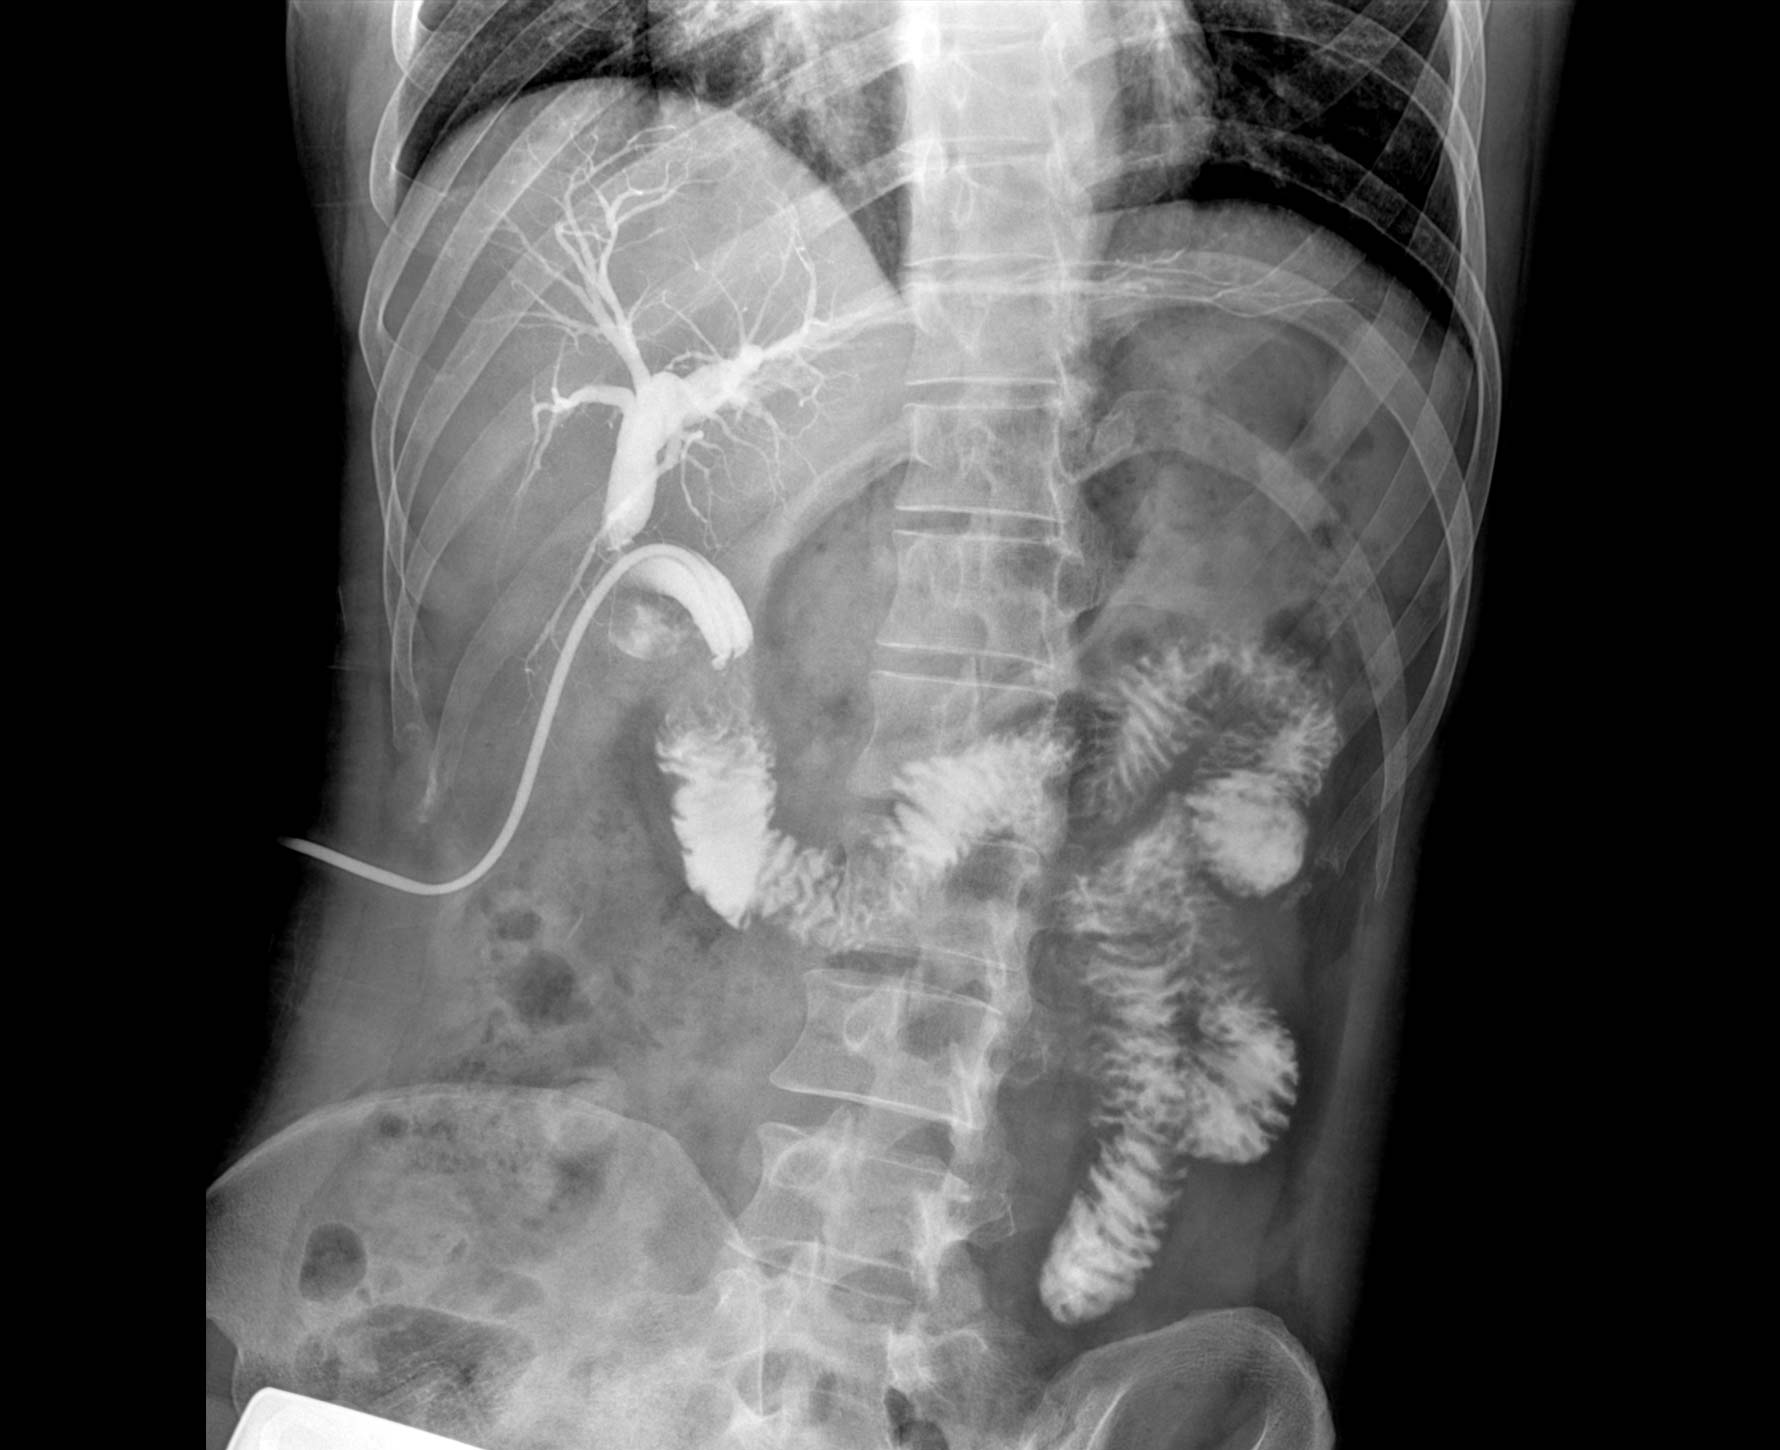

適用于各種普通

及特殊胃腸造影檢查

對胃腸造影檢查影像實時保存,多次回放以便確定病灶部位,患者確診好幫手,減少漏診。